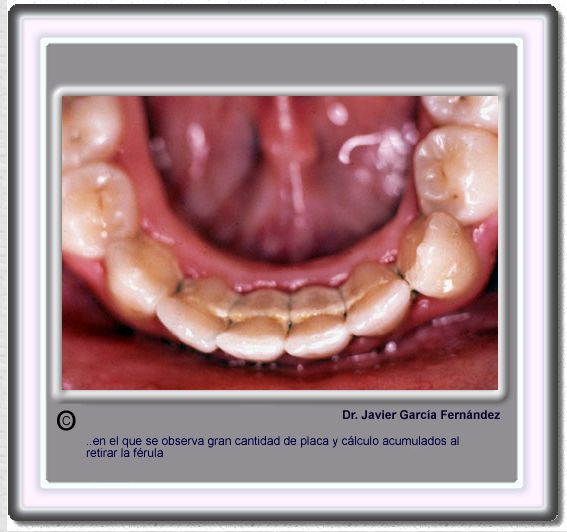

image383